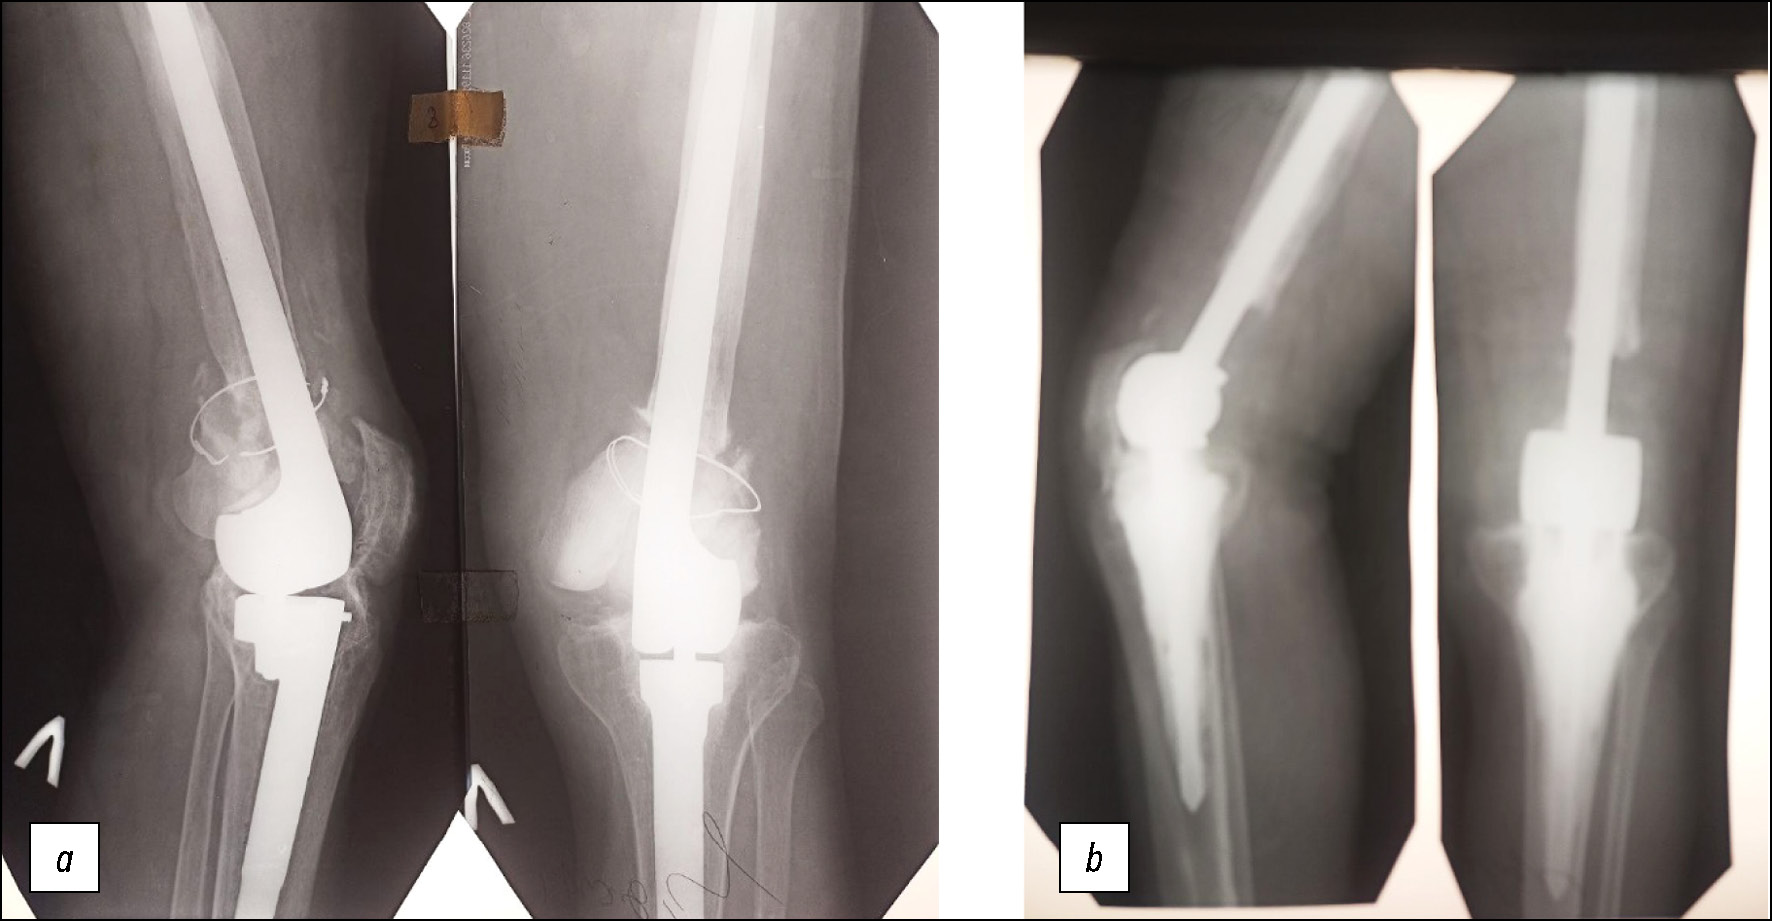

В Центральном институте травматологии и ортопедии (ЦИТО) им. Н.Н. Приорова была диагностирована остеобластокластома дистального отдела левой бедренной кости (по современной классификации — гигантоклеточная опухоль) (рис. 1а), и пациента госпитализировали в городскую клиническую больницу № 59 г. Москвы, в клинику травматологии и ортопедии, которую возглавлял лауреат Государственной премии СССР профессор Айдын Саларович Имамалиев, заведовавший кафедрой травматологии, ортопедии и военно-полевой хирургии Московского медицинского стоматологического института им. Н.А. Семашко и лабораторией консервации органов и тканей ЦИТО им. Н.Н. Приорова.

Рис. 1. Рентгенограммы коленного сустава: а — до, b — после аллопластики дистального конца бедренной кости.

Fig. 1. Radiographs of the knee joint: a — before, b — after alloplasty of the distal end of the femur.

11 декабря 1979 года пациенту была произведена резекция дистального суставного конца левой бедренной кости на протяжении 12 см с замещением дефекта аналогичным аллотрансплантатом, консервированным при температуре минус 70 градусов. Как показали экспериментальные исследования и клинические наблюдения, проведённые А.С. Имамалиевым, этот режим консервации был наиболее благоприятным для сохранения биологических свойств трансплантата, его сращения с материнской костью, предотвращения лизиса и сохранения прочности. Трансплантат зафиксировали к материнской кости внутрикостно кортикальным штифтом (рис. 1b). Связочный аппарат сустава восстановили с помощью лавсановой ленты. В послеоперационном периоде 3 дня осуществляли дренирование области операции, а после заживления раны был проведён курс ЛФК на функциональной шине. Через 3 недели после операции пациенту наложили кокситную гипсовую повязку и выписали его на лечение по месту жительства с рекомендацией продолжить иммобилизацию до 6 месяцев.